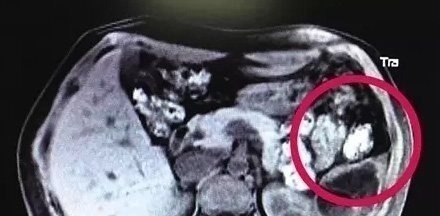

医生怀疑胎儿是掉到了其他部位,便建议她检查一下其他器官。随后王婷便做了肝胆胰脾肾超声检查。最后医生在脾脏部位发现了一个活生生的胎儿。

过了几天,王婷的脾脏部位明显开始疼痛,医生决定立即进行手术。经过2个多小时的手术,王婷的下半部脾脏连同胎儿被切除,胎儿已经和3个月的胎儿差不多大了,还长出了头、脸、鼻、眼睛、四肢等。(以上图片均来源于网络)